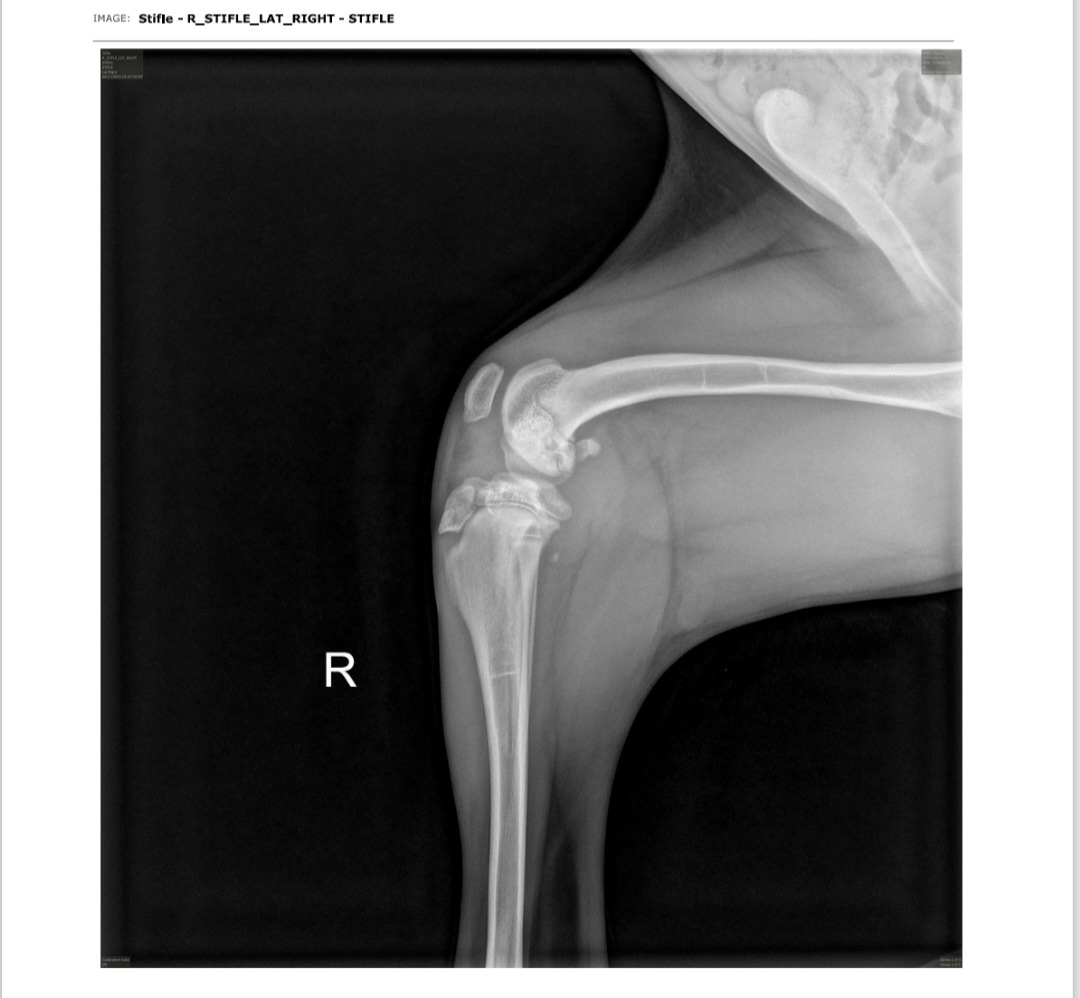

Due to an unknown injury or likely a genetic defect Bodhi was diagnosed with OCD (Osteochondritis dissecans). It was originally thought to be mild and would heal on its own. Unfortunately, his knee has rapidly and unexpectedly deteriorated in the span of a few weeks and will need surgery to stabilize the entire joint. Procedures include - a TPLO (Tibial Plateau Leveling Osteotomy) and a MPL (Medial patellar luxation). The bone/cartilage malformation will also have to be removed.